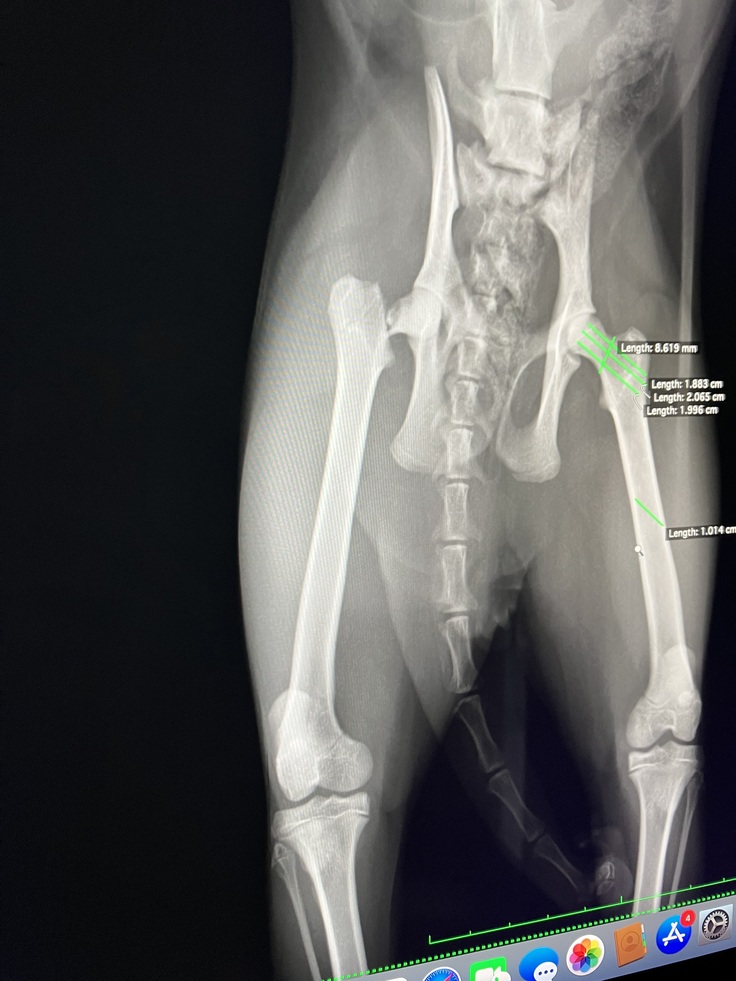

結果は股関節の骨が折れている可能性が高いと

レントゲンの写りが悪く正確なことは伝えられませんが残りの1割の骨で繋がっている状態じゃないかと言われました。先生は熱心な方でしたが

診断結果は、右股関節骨頸部骨折

近年ではよく洋猫に多くあるみたいです

(B病院の診断書、下)

(B病院でのレントゲン写真①②、下)

①

②

手術内容:大腿骨頭骨折整復術